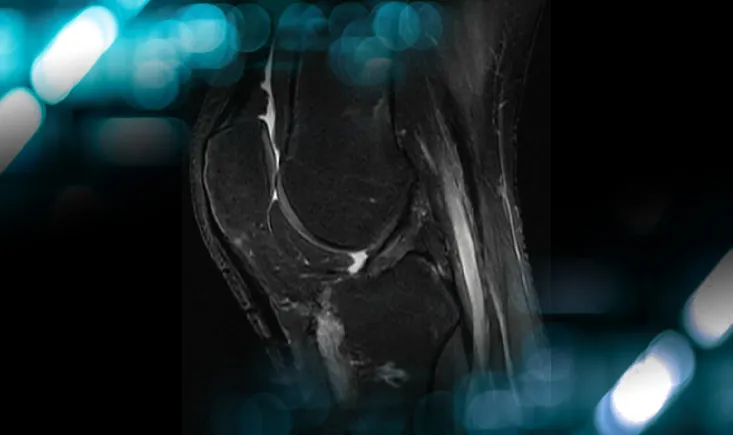

Management of an osteolytic lesion of the distal femur affecting the knee joint

Explore the case of a patient with knee pain, revealing more than just an injury, and uncover the management strategies for osteolytic lesions…